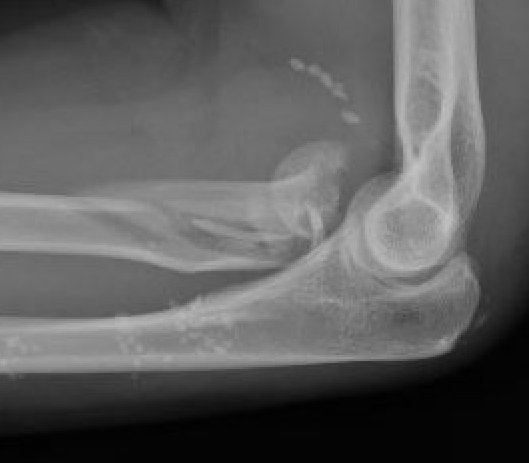

Completely displaced radial neck fracture

ORIF with plates